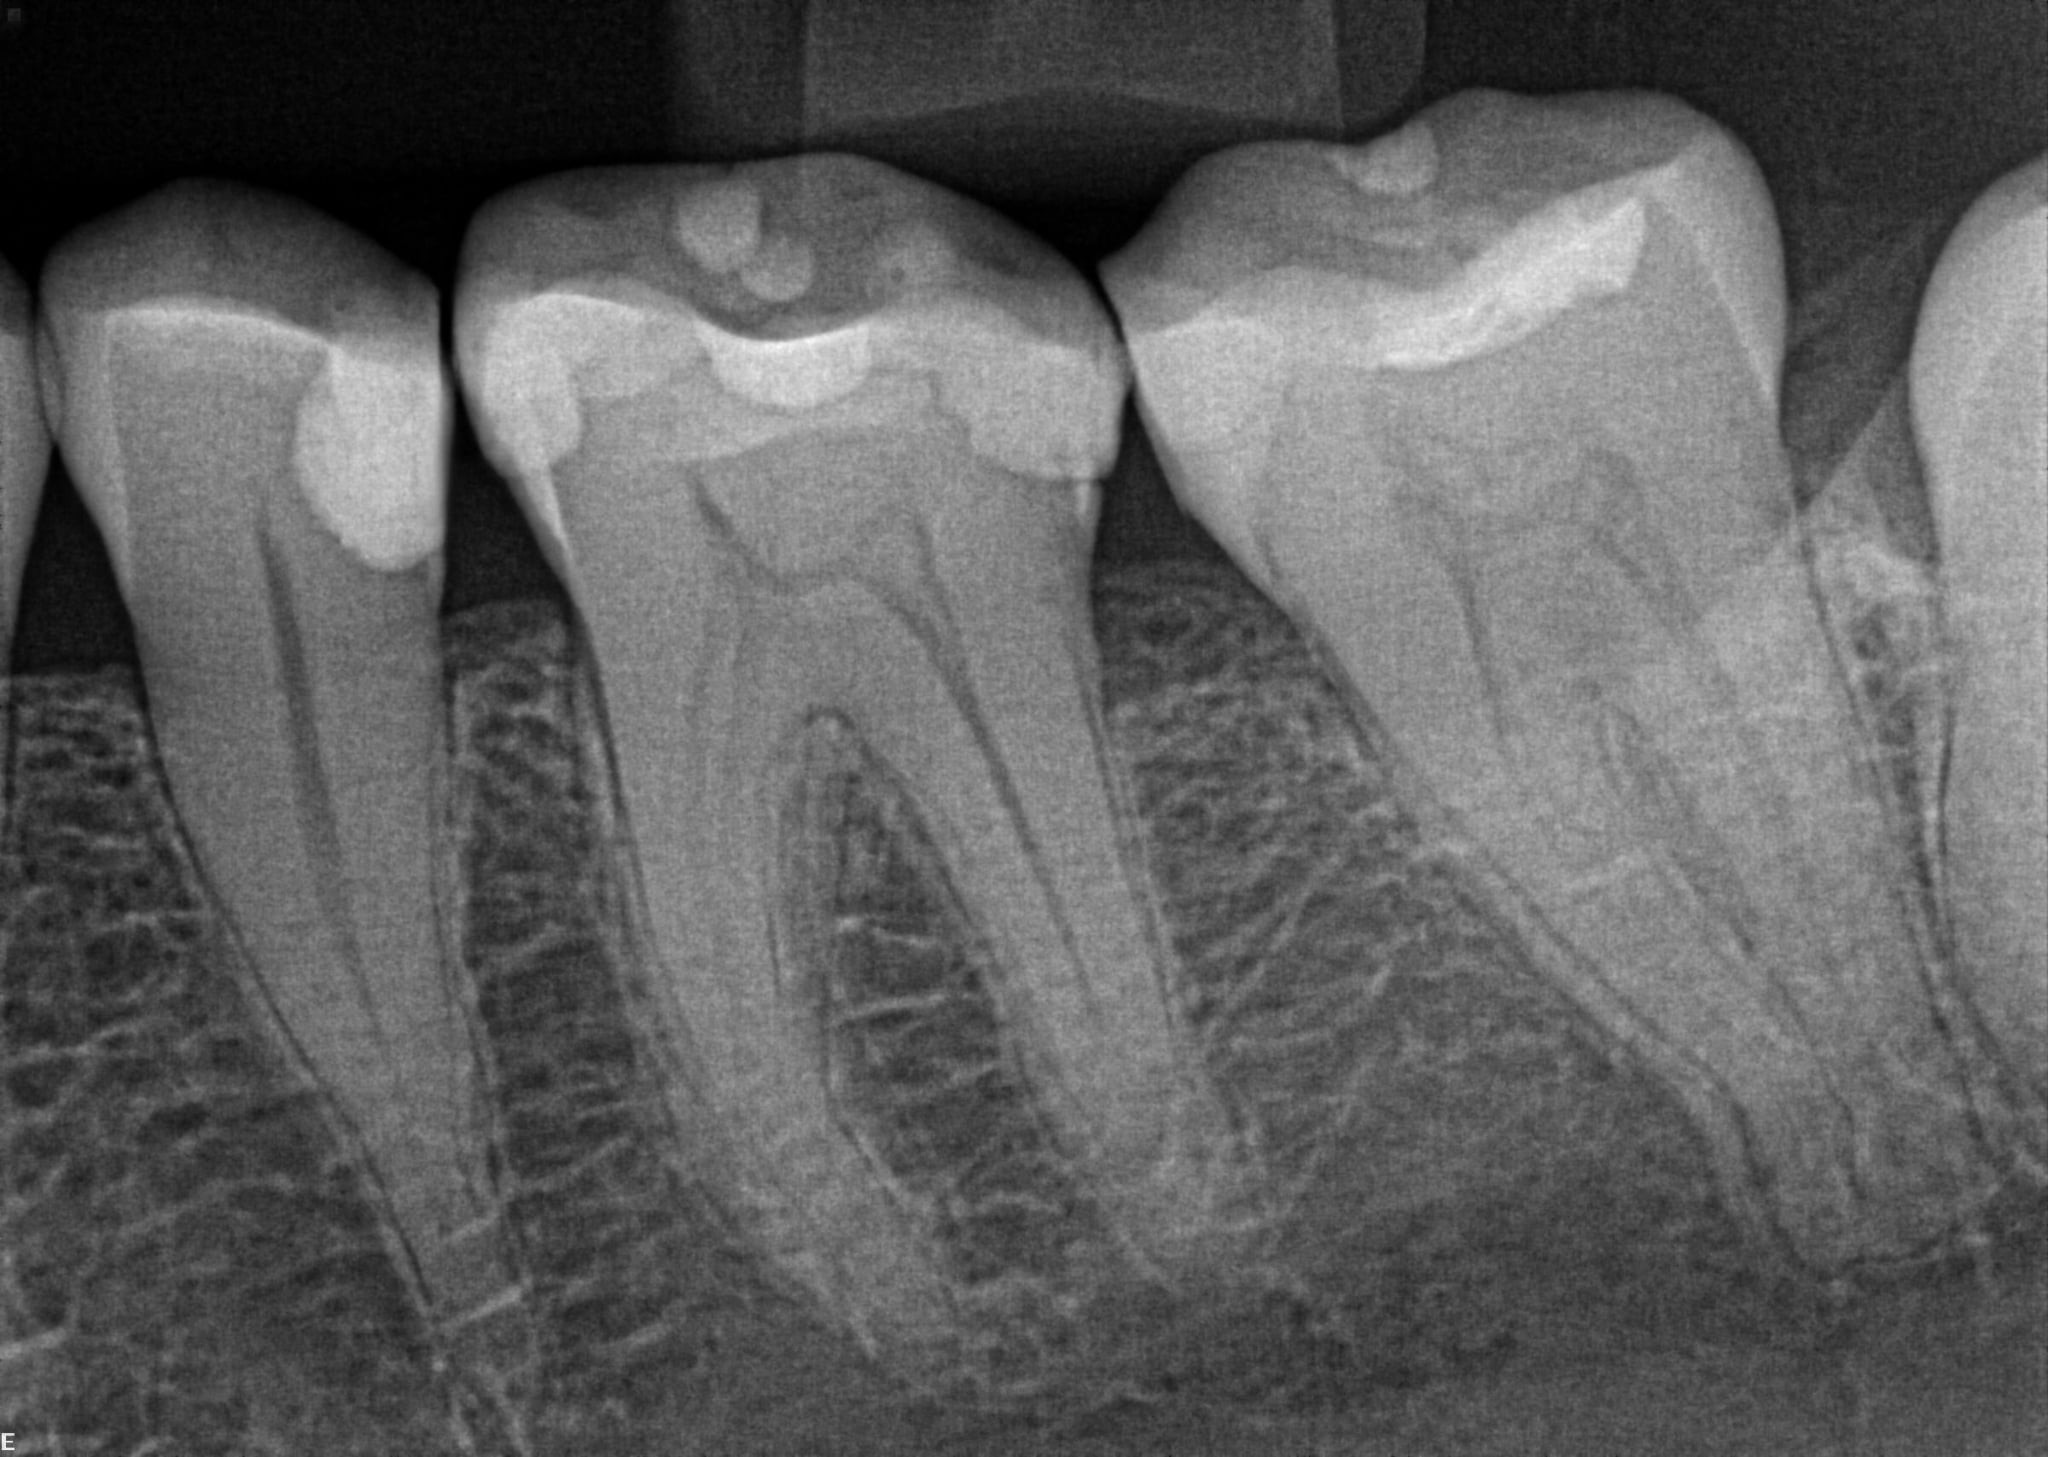

The radiograph shows evidence of

The radiograph shows evidence of calculus on